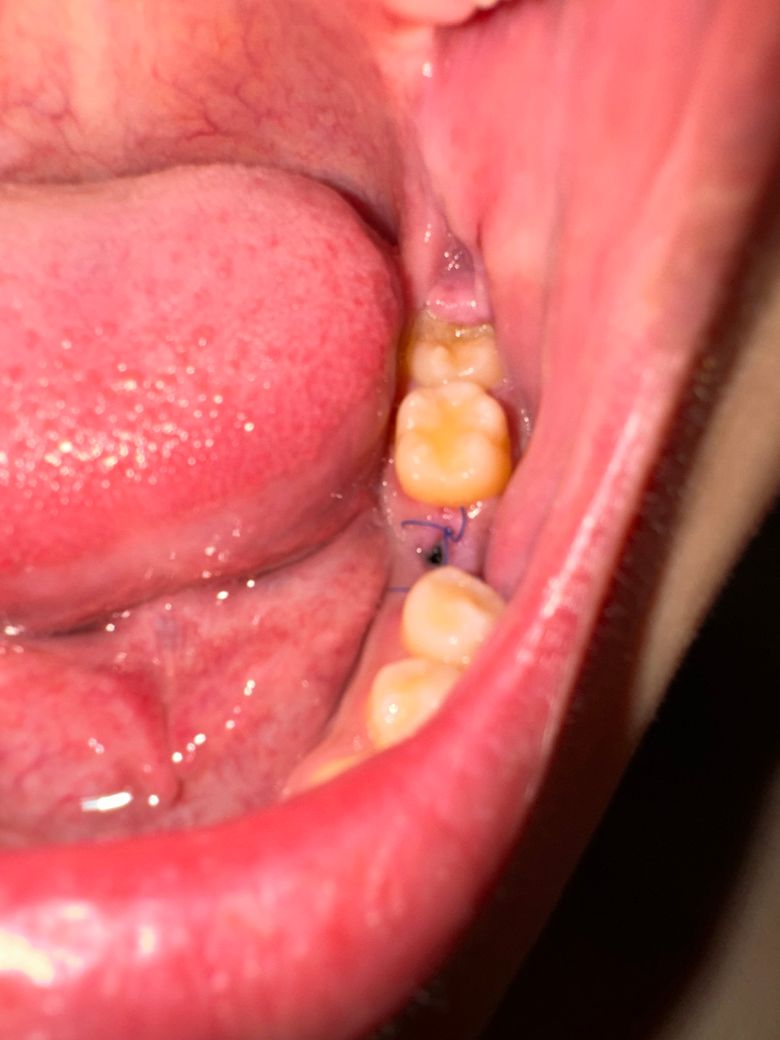

치조골수술 임플란트 식립 동시진행한지 12일 지났습니다

잇몸살이 벌어졌고 안쪽 임플란트가 살짝 보일정도입니다..

이럴경우 경과가 어때보이나요?

실패할 가능성이 높나요?

사진상으로는 크게 문제가 잇어 보이진 않습니다. 하지만, 임플란트 나사가 보인다면 치과에 가셔서 엑스레이를 찍어보셔야될것같습니다.

사진으로만 봐서는 크게 문제가 없는 것으로 보입니다. 고리식을 하고 임플란트를 한 부위에 잇몸에는 상처가 있기 때문에 상처가 아무는 동안 해당 부위가 자극되지 않도록 관리를 해주는 것이 좋습니다

1. 일단, 지금 잇몸이 살짝 벌어져 있는 것은 전체 임플란트 치료의 성공,실패에 있어서 큰 영향은 미치지 않을 것 같습니다.

2. 임플란트 수술 후 잇몸 상처는 1~2주 정도 지나면 초기 치유가 이뤄집니다.

3. 임플란트는 안쪽에서 잇몸뼈와 융합되고, 잇몸 상처는 나을때까지 2~3달 정도 시간이 걸립니다.

4. 초기 잇몸 치유를 도와주도록 봉합을 하는데 봉합이 좀 느슨한 경우 잇몸이 벌어질 수도 있습니다.

현재 잘 아물고 있는 것으로 보이며, 아무는데까지 2-4주정도 시간이 필요로 됩니다.

잘 아물수 있도록 흡연 및 음주는 피하고, 맵고 자극적인 음식도 피하길 권합니다.